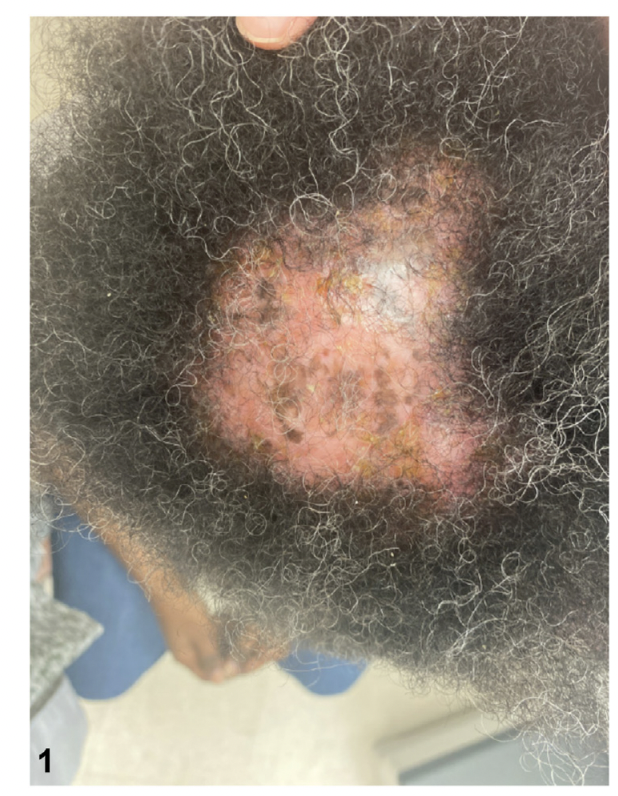

Scalp sarcoidosis resembling central centrifugal cicatricial alopecia. The patient had a history of lung sarcoidosis and had skin lesions consistent with cutaneous sarcoidosis. Image from Prohaska J et al. Scalp Sarcoidosis Presenting as Cicatricial Alopecia. J Am Osteopath Assoc . 2018 Dec 1;118(12):824-826. Image used with creative commons license.

Clinically, the lesions often have an orange color. They do not always especially in darker skin types. It’s important to realize that scalp sarcoidosis truly is one of the great imitators and can take on many many different appearances! and may look very similar to lichen planopilaris, discoid lupus, pseudopelade, central centrifugal cicatricial alopecia, acne keloidalis, folliculitis decalvans, necrobiosis lipoidica, scleroderma or even alopecia areata at first glance. Some present like diffuse scaling and some present with ulcerations. Just like the skin lesions (which we’ll review below), scalp sarcoidosis can take on many forms!

One of the fastest ways to get clues about a possible diagnosis of scalp sarcoidosis might be present in a patient with hair loss is to look for the skin sarcoidosis that is present elsewhere or ask about a history of systemic sarcoidosis. Most patients with scalp sarcoidosis have other clues!